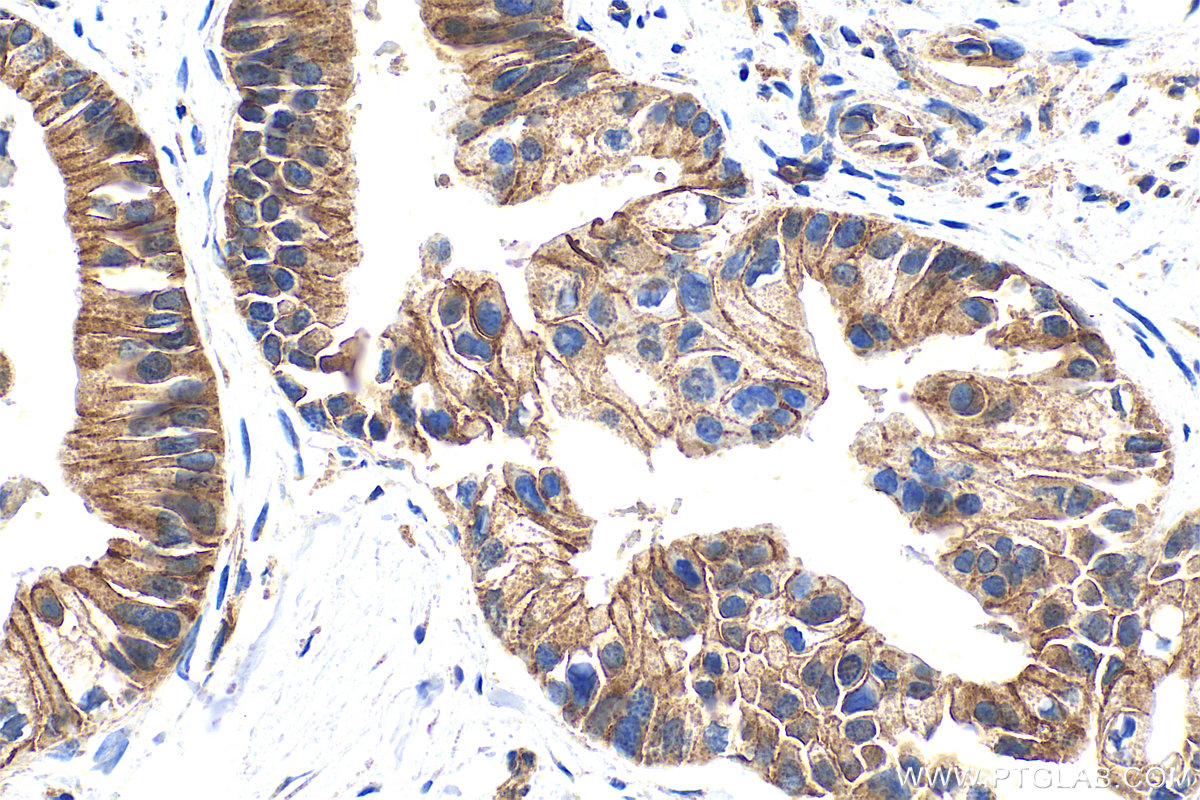

| Positive IHC detected in | human pancreas cancer tissue, human lung cancer tissue Note: suggested antigen retrieval with TE buffer pH 9.0; (*) Alternatively, antigen retrieval may be performed with citrate buffer pH 6.0 |

| Immunohistochemistry (IHC) | IHC : 1:200-1:800 |

25900-1-AP targets ADAM10 in WB, IHC, IF, ELISA applications and shows reactivity with human, mouse samples.